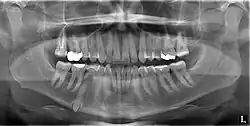

Mandibular canine impacted in the chin

An impacted tooth is one that fails to erupt into the dental arch within the expected developmental window. Because impacted teeth do not erupt, they are retained throughout the individual's lifetime unless extracted or exposed surgically. Teeth may become impacted because of adjacent teeth, dense overlying bone, excessive soft tissue or a genetic abnormality. Most often, the cause of impaction is inadequate arch length and space in which to erupt; that is, the total length of the alveolar arch is smaller than the tooth arch (the combined mesiodistal width of each tooth). The wisdom teeth (third molars) are frequently impacted because they are the last teeth to erupt in the oral cavity. Mandibular third molars are more commonly impacted than their maxillary counterparts.